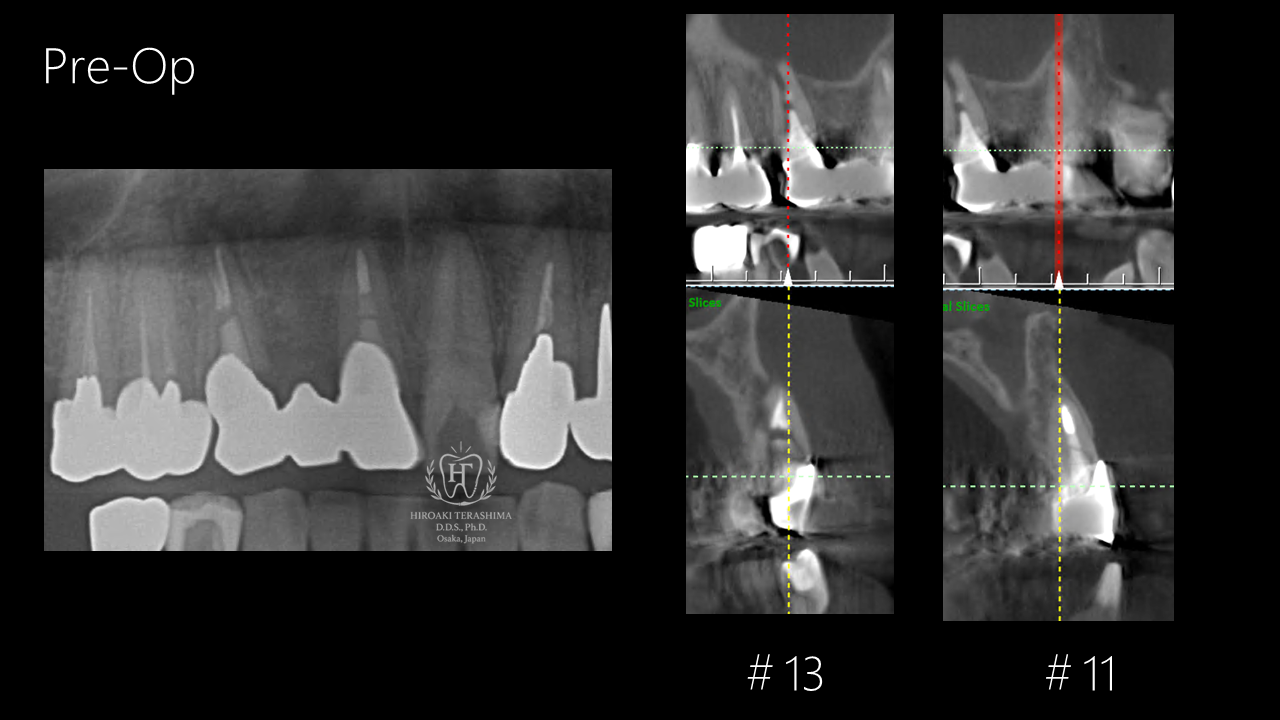

■ 術前の状態

ブリッジの支台歯に歯根破折を認め、保存は困難な状態でした。

- 診断:歯根破折